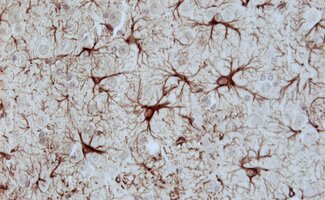

Astrocytes

Astrocytes belong to the most abundant cells in the mammalian central nervous system (CNS).